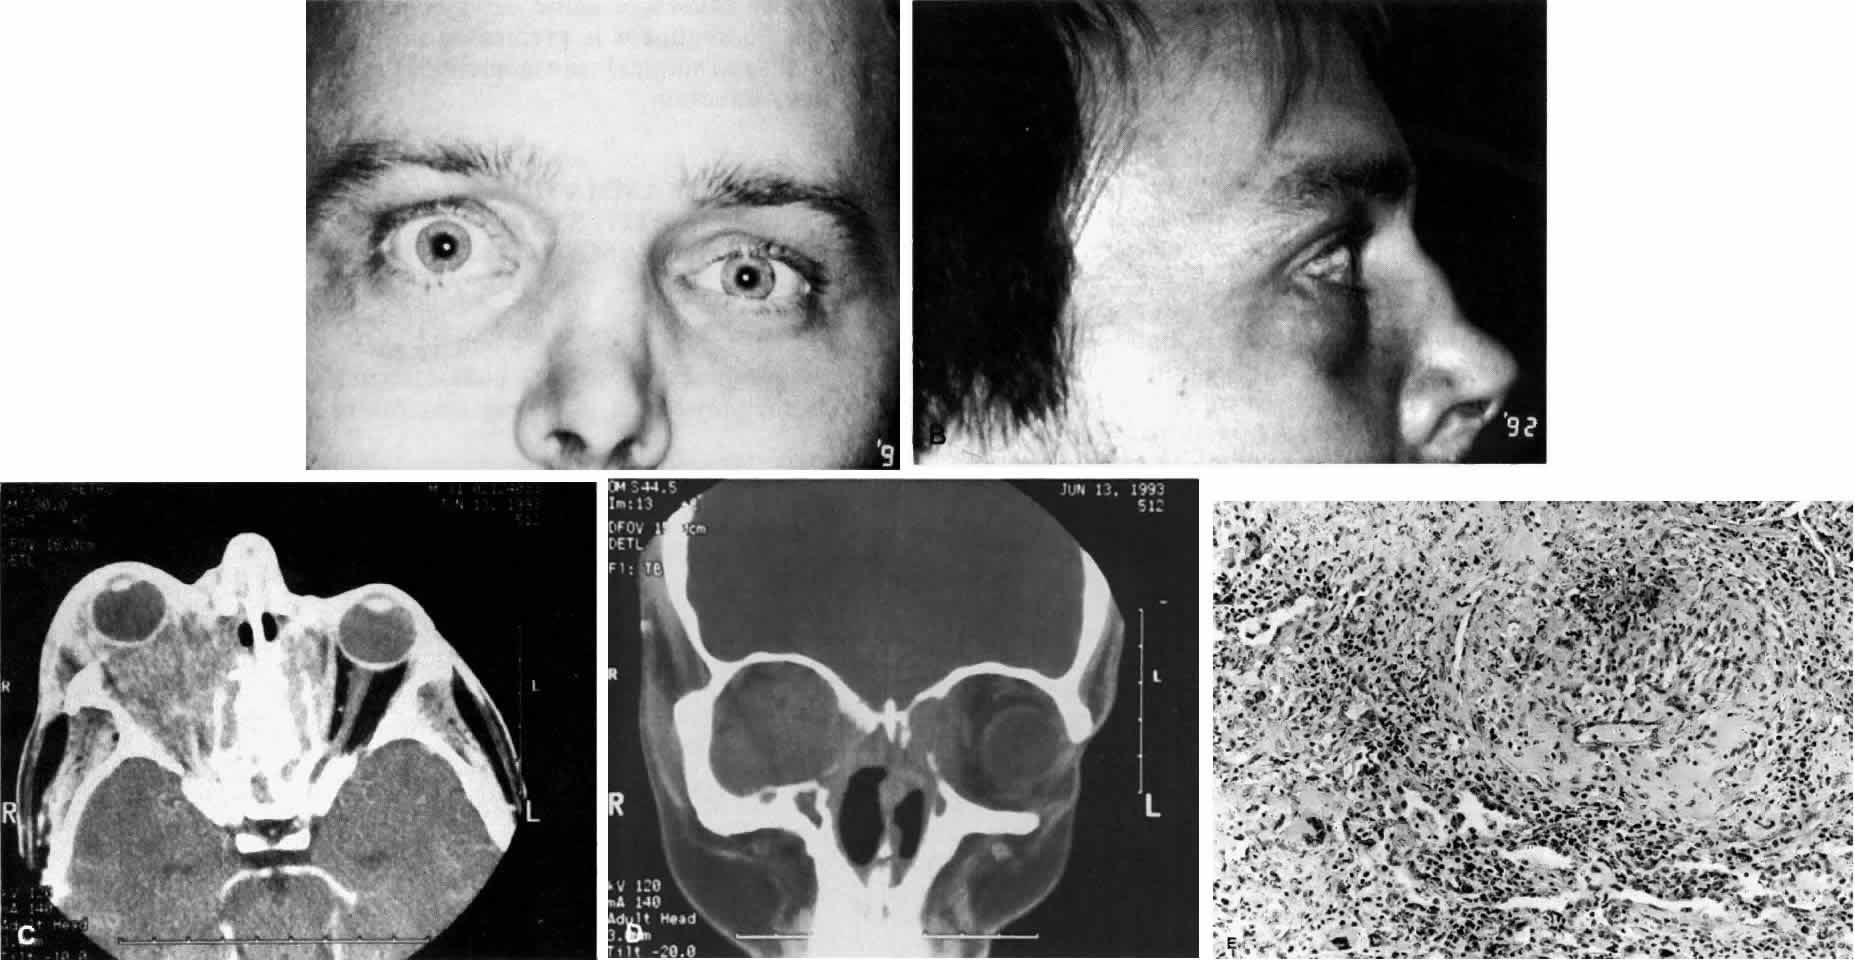

Fig. 11. A. This 31-year-old man has had Wegener's granulomatosis for 2 years. His disease process is stable on chronic corticosteroid therapy. He has no evidence of systemic disease. Note right-sided proptosis and hyperglobus. B. Profile of same patient demonstrating collapse of nasal bridge from bony destruction secondary to Wegener's granulomatosis. Note presence of swelling in lower eyelid. C. Axial CT image from the same patient demonstrating significant bilateral disease and bony destruction. Despite the extent of the orbital process on the right, the patient does not have diplopia. D. Coronal CT image showing destruction of medial orbital walls, vomer, and orbital septum. E. Pulmonary biopsy specimen from patient with orbital signs contains an almost obliterated vessel to right of center and scattered giant cells on left (H&E, ×160).

Ocular manifestations include orbital inflammation, scleritis, keratitis, and uveitis. The ocular involvement can occur from extension of sinus and nasal lesions or from focal small vessel vasculitis.